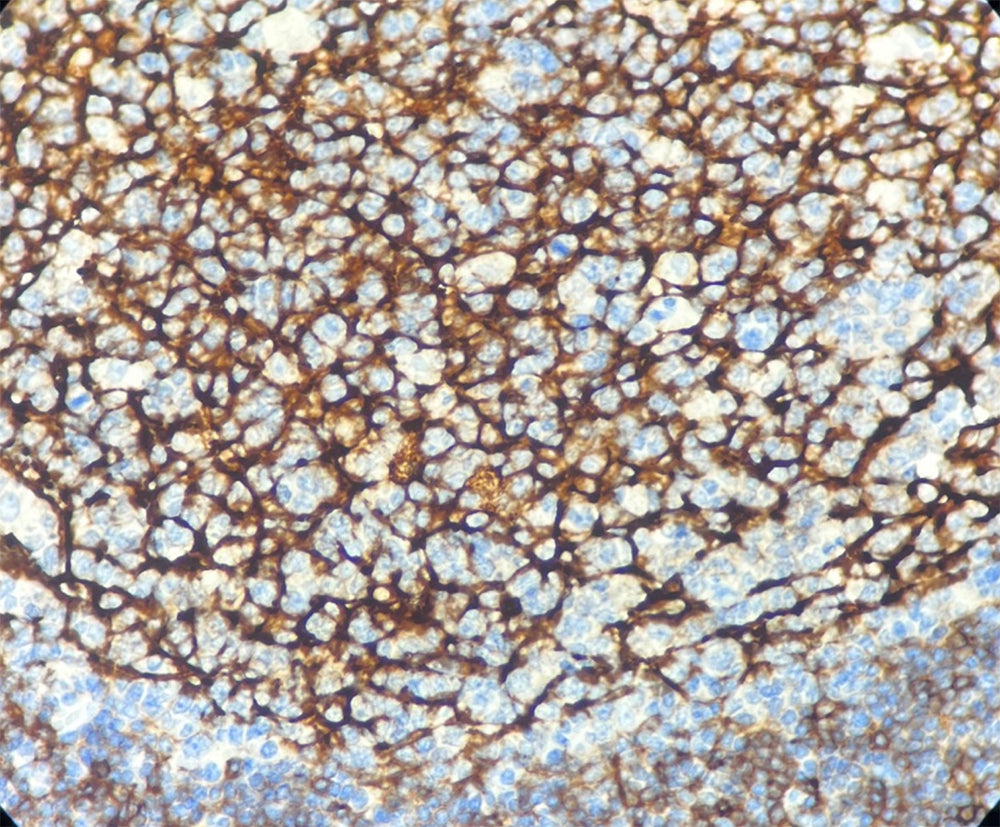

Localisation : Membrane cellulaire

CD23, récepteur de basse affinité des IgE, appartient à la famille des lectines de type C et joue un rôle important dans les réactions allergiques, la défense immunitaire contre les parasites et la régulation des taux d’IgE.

Il est spécifiquement exprimé à la surface des lymphocytes B matures, des macrophages activés, des éosinophiles, des cellules dendritiques folliculaires et des plaquettes.

L’anticorps CD23 est un marqueur important pour l’identification des néoplasies à cellules B : la positivité du CD23 est fréquemment observée dans la leucémie lymphoïde chronique B (LLC-B) et le lymphome lymphocytique à petites cellules (SLL), tandis que le lymphome du manteau et le lymphome à petites cellules clivées sont généralement négatifs.

Contrôle positif : Tissu amygdalien